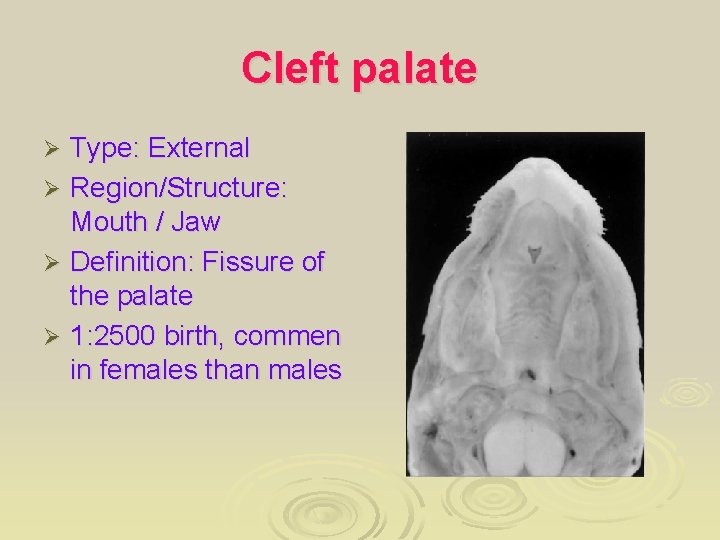

Cleft palate Type: External Ø Region/Structure: Mouth / Jaw Ø Definition: Fissure of the palate Ø 1: 2500 birth, commen in females than males Ø